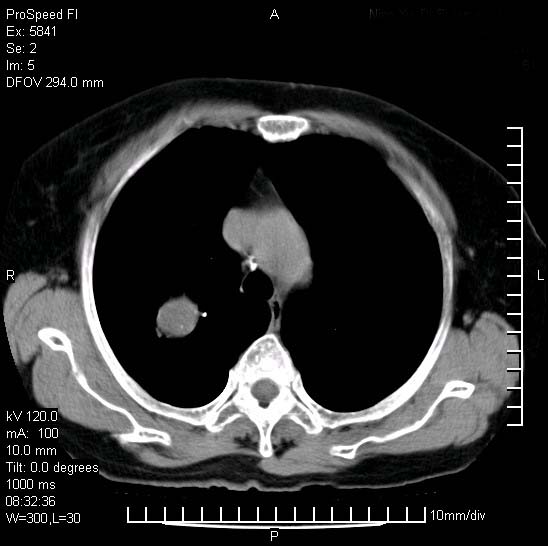

胸痛,咳嗽,气短一周,无发热。右上肺见一结节灶,边缘刺角,内见多个小钙化结节。考虑结核球?肿瘤? 余无异常没有上传。

考虑右肺上叶继发性肺结核,结核球形成。

建议:追踪复查。